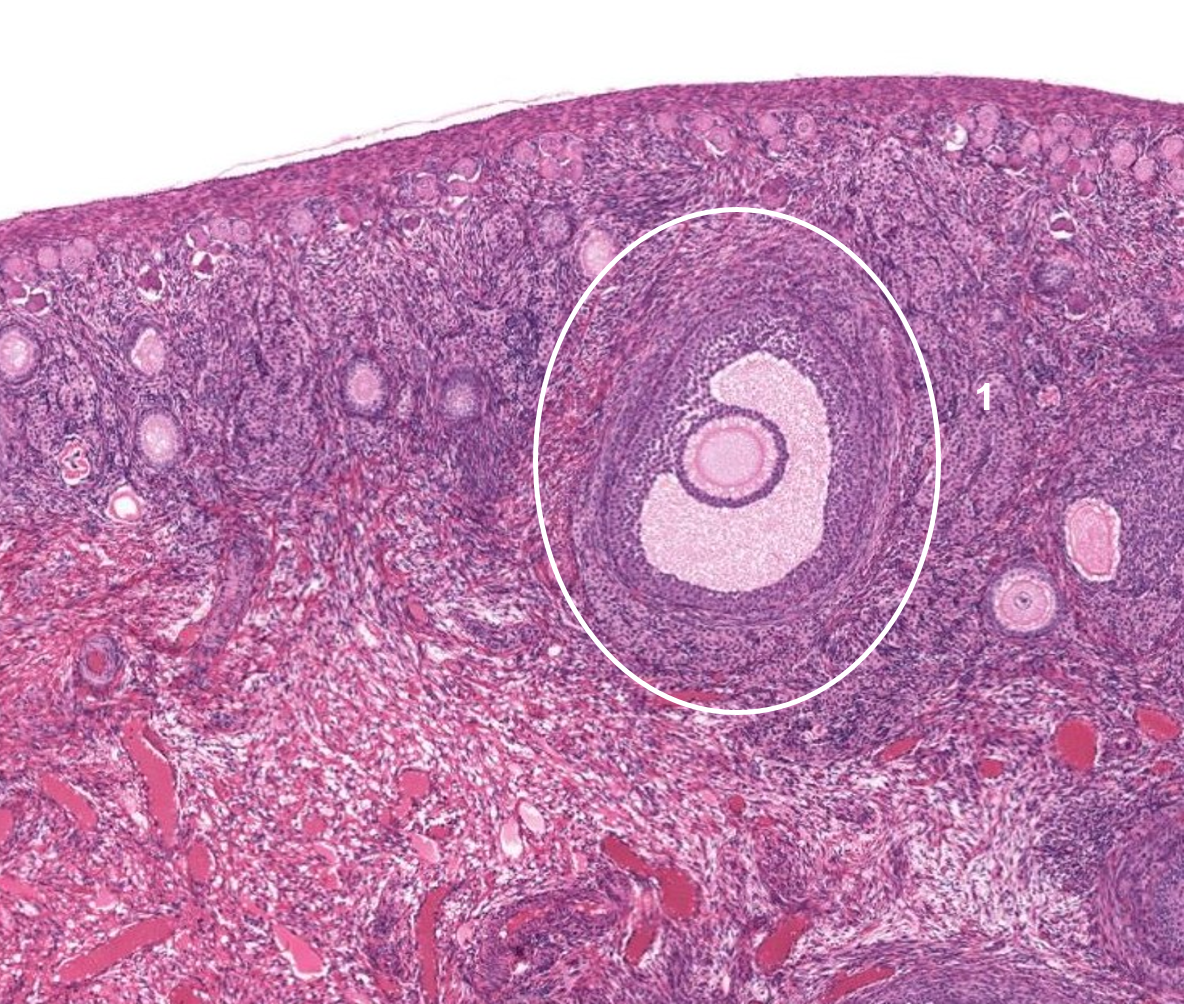

Ovário - folículo primordial

Ovário - folículo secundário

Ovário